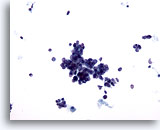

画像 4

肺FNA、肺腺癌

波状縁を呈する悪性腺細胞の集塊。背景には何も見られず、腫瘍性背景を呈していません。悪性細胞の保存状態は良好です。細胞質には、離散性の空胞が微細なものから大きなものまで見られ、一部には取り込まれている好中球が認められます。 60倍

画像 4

肺FNA、肺腺癌

波状縁を呈する悪性腺細胞の集塊。背景には何も見られず、腫瘍性背景を呈していません。悪性細胞の保存状態は良好です。細胞質には、離散性の空胞が微細なものから大きなものまで見られ、一部には取り込まれている好中球が認められます。

60倍